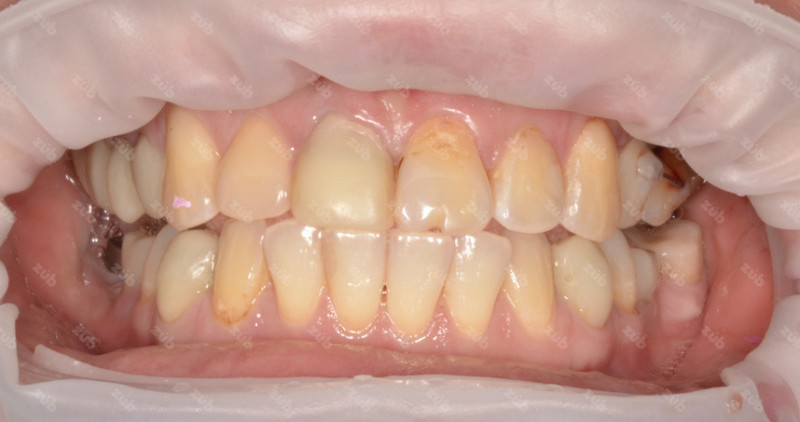

Стоматология ЗУБ (ZUB)

Профгигиена

Все работы клиники